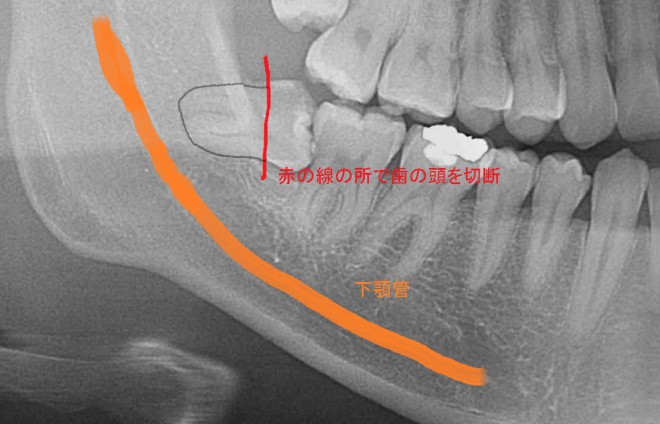

歯の頭を切断しなくてはなりませんがこの時に下顎神経の位置をしっかり把握しておかないといけません

最後の抜歯の段階で無駄な力を与えると下顎神経を圧迫し唇の麻痺が起きてしまいます